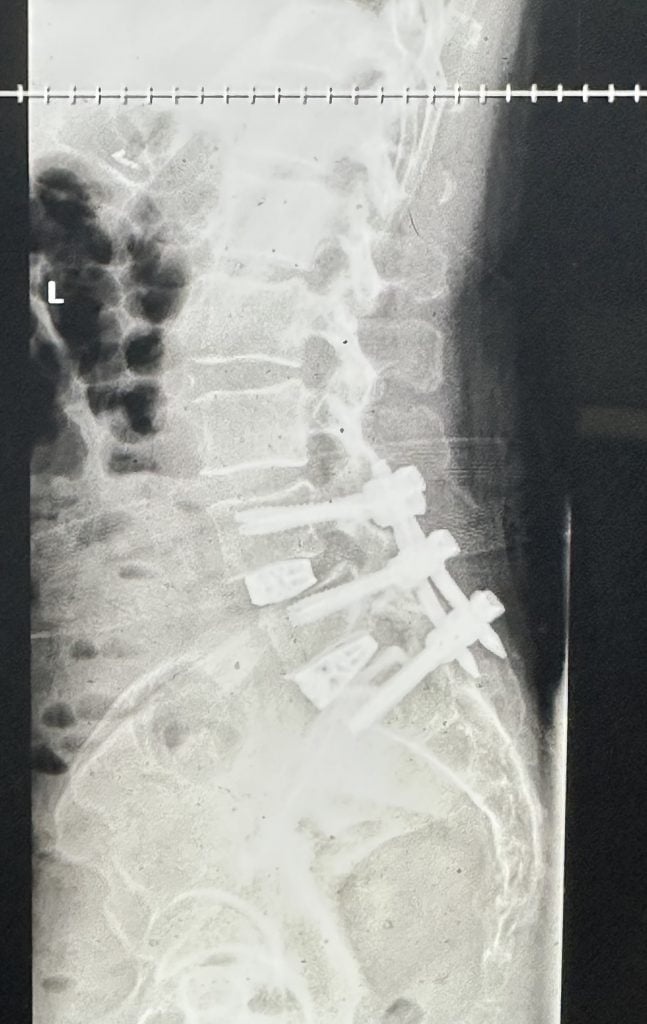

ALIF Surgery: Anterior Lumbar Interbody Fusion

I had been suffering for eight years from chronic, horrific pain in the lower back and pelvis. It was pain of indescribable intensity. Dr. Lebl gave me the correct diagnosis and performed ALIF surgery to fuse the anterior lumbar parts. The operation was successful and I got rid of all previous pains, and even my psychological state improved. I felt very happy. Dr. Lebl is a human being before he is a doctor. No matter what I say, I will not give him his due thanks and appreciation. He has all my love, thanks, appreciation and respect. He and his medical team at the time of surgery, the pain doctor Emilia, and the physical therapists Thomas and Erika, and everyone have all my thanks and appreciation. I will never forget Dr. Darren Lebl for the rest of my life.